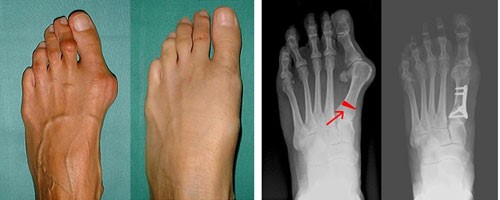

Hallux Valgus (Халюс Вальгус) або вальгусна деформація стопи – патологія, яка характеризується прогресуючим вальгусним відхиленням першого пальця стопи, в результаті чого змінюється анатомічна вісь стопи та пальців.

При вальгусній деформації стопи, великий палець нахиляється всередину до менших пальців, внаслідок на стопі відбувається випинання головки кістки, і формування кісточки або шишки на нозі в області нижньої частини пальця. Саме тому пацієнти часто називають патологію – кісточка або шишка на великому пальці ноги.

Основним способом позбавлення від вальгусной деформації першого пальця стопи є операція з видалення «кісточки» на нозі, резекційна артропластика або остеотомії.